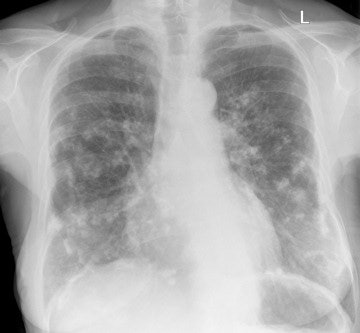

In parenchymal disease, asbestos-induced pulmonary fibrosis usually occurs 20 to 30 years after high levels of exposure. It progresses even after exposure cessation and causes progressive restrictive lung function. Asbestosis appears as interstitial reticulation and "shaggy heart" on chest x-rays, while subpleural reticulation, branching linear peripheral opacities, and "honeycombing" can be seen on high-resolution CT, they pointed out. Parenchymal bands and subpleural curvilinear opacities are less specific CT features. This condition is compensable.